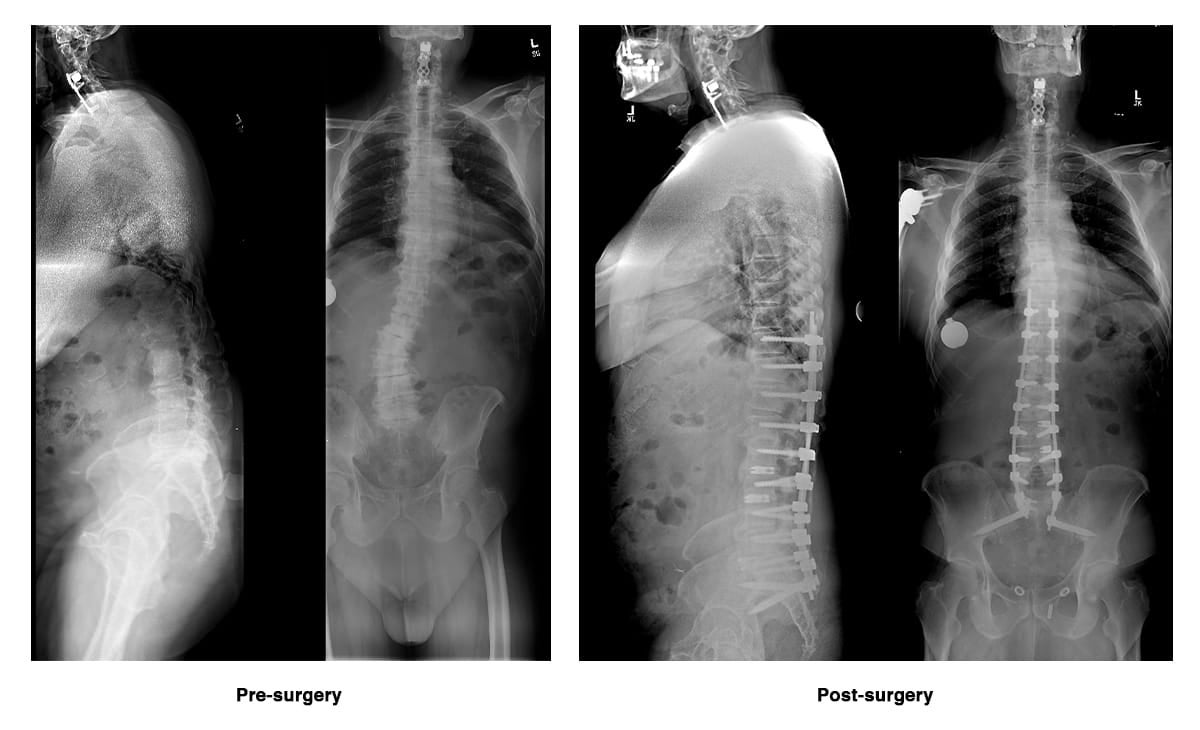

The procedure involved stabilizing his spine with titanium implants and correcting his posture to reduce nerve compression. His recovery required dedicated rehabilitation, including both inpatient and outpatient physical therapy, but the results came quickly.

Within weeks, Eric’s pain was gone. At his one-year follow-up, scans confirmed his spine had healed well, with bone growth stabilizing the implants. “I feel like I got my life back,” Eric said. “I can stand tall, walk without pain, and enjoy everyday activities again. It feels like a miracle.”